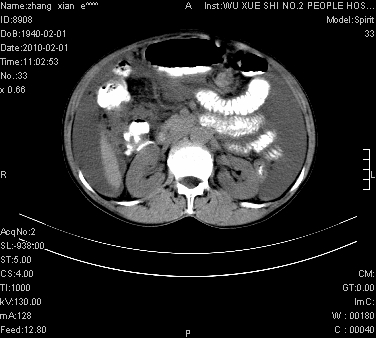

标题: CT24434:70岁 女 腹胀,腹水原因待查 [打印本页]

标题: CT24434:70岁 女 腹胀,腹水原因待查

腹盆腔大量积液,子宫增大,子宫颈增大外形不规则,内见低密度影,膀胱后壁显示不清,右腹股沟肿大淋巴结,脾脏囊性占位,子宫颈占位,子宫颈癌?建议增强。

考虑:1、腹膜转移,大量腹水;

2、脾占位性病变;

3、左侧卵巢占位性病变,建议增强进一步检查。

大量腹水,右肾、脾囊肿可能性大          考虑左侧附件区占位,建议增强